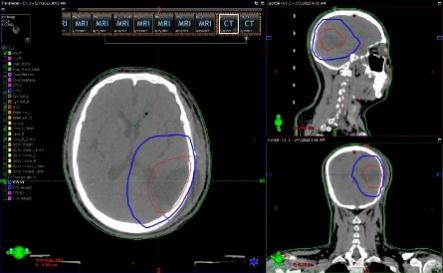

第四步:医生进行靶区勾画以及放疗的处方剂量确定

完成定位后,放疗科医生在计算机图像前确定靶区(即需要放疗照射的肿瘤区域),通过放疗专用TPS软件,在模拟定位扫描的CT上,逐层确定靶区的范围。这不仅需要医生对肿瘤的影像学、病理生物学等有深入的理解,还要有丰富的临床经验。医生要确定需要照射的肿瘤靶区,还要找出需要保护的正常组织范围。

放疗做膜是什么意思精准放疗!八步读懂放疗流程_https://www.jmylbn.com_新闻资讯_第10张

靶区确定后,医生需开出放疗处方,包括:肿瘤照射剂量、照射次数,正常组织最大的接受剂量等。